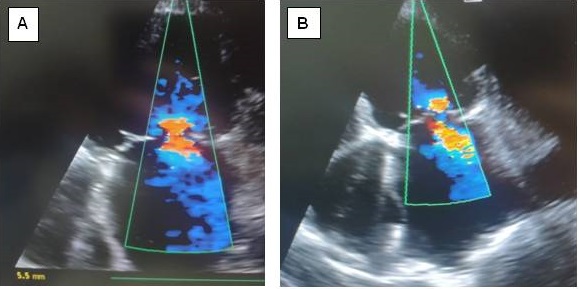

Fig. 1. Visualization of Mitral Insufficiency using color Doppler imaging before the surgical intervention: A — before insertion of Intra-Aortic Balloon Counterpulsation; B — with the working Intra-Aortic Balloon Counterpulsation in the early postoperative period.

Group 1 included 132 patients (91 men and 41 women) whose revascularization procedure was coronary artery bypass surgery. The average LVEF was 34.1 ± 4.6% (minimal 26%, maximal 42%). In 89 patients, III degree MR was recorded before IABC support, 27 patients — II degree MR, and 16 patients — I degree MR (Table 1, Fig. 1A).

In group 1 with the application of IABC, a statistically significant reduction in the degree of MIn (based on the change in the diameter of the v.c.) by 58% (р < 0.05) in the early postoperative period (Fig. 1B) and by 54% (р < 0.05) more than six months after the surgical intervention. This parameter remained at this level for a long observation period, with a minimum of 12 months.